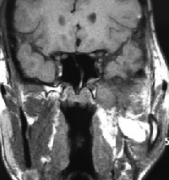

一位38歲女性,以三叉神經(jīng)瘤表現(xiàn)為左側(cè)面部感覺異常。診斷是基于磁共振成像(MR)的發(fā)現(xiàn)。應(yīng)她的要求,伽瑪?shù)斗派渲委?GKR)在另一家醫(yī)院進(jìn)行。GKR術(shù)后15個(gè)月,隨訪的MR影像顯示腫瘤重...

三叉神經(jīng)鞘瘤表現(xiàn)為錯(cuò)頜畸形,Glasauer和Tandon報(bào)道青少年三叉神經(jīng)鞘瘤的發(fā)病率至少為10%,而Goet以及其他人。圖3:術(shù)前磁共振成像圖描述:對(duì)比T1加權(quán)磁共振成像與52×78×51厘米的軸向、矢...